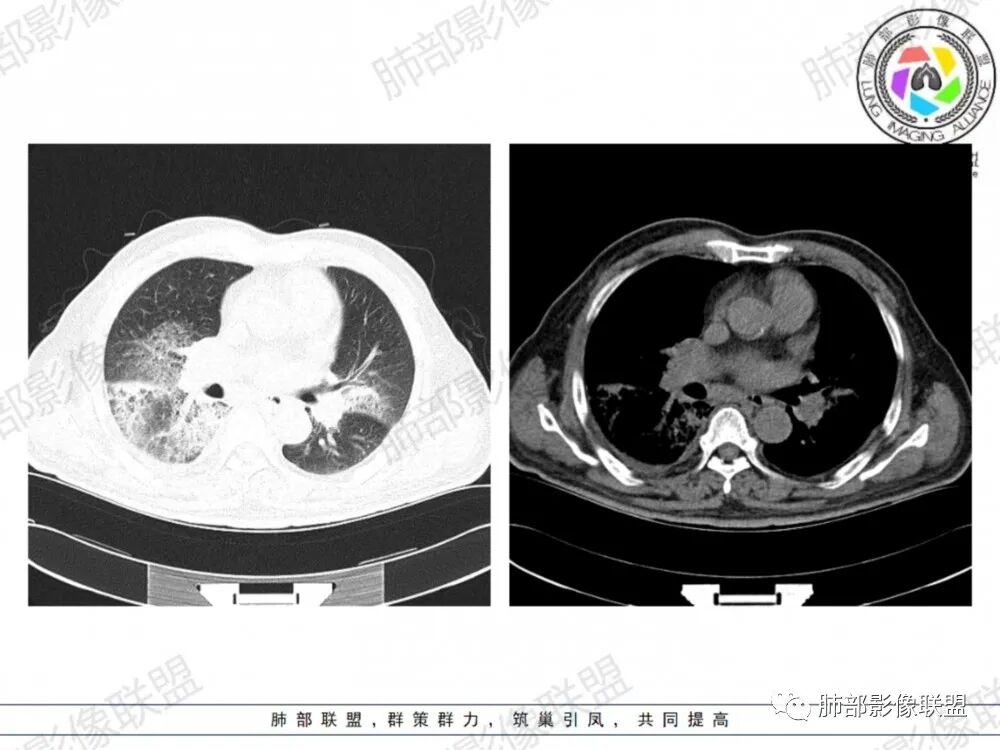

晨读:老年男性患者,咳嗽气喘3天入院,伴有发热,体温38.2℃,有糖尿病,高血压病史,有长期吸烟史,近期旅游史,白细胞,中性粒,CRP,PCT增高,肝功能损害,血气分析:低氧血症,胸部CT:双上肺及右下肺实变密度影伴周围磨玻璃密度影,边界整体清楚,内部支气管走形自然,伴双侧少量胸腔积液,综合考虑感染性病变,重症社区获得性肺炎,重点考虑非典型病原体,军团菌可能,鉴别肺克,结核合并感染

晨读老年患者,咳嗽气喘三天,腹泻,有多脏器的损害。有基础病的病史,糖尿病,高血压。旅游病史。两位靠后分布的大片状的实变影及磨玻璃样阴影,跨叶小叶性的分布,支气管充气征。内部的小叶间隔局部增厚。纵隔淋巴结不大,右侧胸腔积液。首先考虑感染性的病变,靠后重力感,肺克雷伯杆菌肺炎。鉴别诊断军团菌肺炎。

双肺多发斑片及大片状高密度影,周围伴磨玻璃影,界欠清晰,内见多发囊状透亮影呈蜂窝状,病变内支气管走形规则,无肺气肿背景,双侧胸腔积液,老年男性,糖尿病史,消化道症状,炎性指标升高,考虑军团菌感染,克雷白杆菌感染待排。

双肺大片磨玻璃影伴实变,边缘清晰,支气管通畅,磨玻璃影部分呈细网格状,胸膜下清晰,双侧胸腔积液,心影增大,心腔密度减低,贫血,考虑肺克,军团菌

胸部CT示双肺弥漫实变影伴周围磨玻璃影,跨叶段分布,可见小叶间隔增厚,支气管充气征,双侧胸腔积液。无明显坏死空洞及树芽征。

CT:双肺多叶段毛玻璃影、实变影、小叶内间质增粗,肺内病变有重力依赖趋势,双侧少量胸腔积液,无空洞、树丫;

军团菌感染可累及多个脏器,肺是主要的受侵器官。军团菌肺炎为广泛多叶分布的炎症。

1.病变复杂多样∶大片状实变影、斑片状模糊阴性,网格状阴性、小结节影。多叶受侵是本病重要影像学特征性改变。

3.呈小叶肺炎状改变,病变大小以肺小叶为单位的支气管肺炎,呈弥漫性的单或双侧分布。局部可融合呈高密度的团片状影像,本病又一典型的影像学特点。

4.病变常伴有胸水出现,肺部阴性多变的情况下伴有胸水形成应高度怀疑军团菌感染的可能。